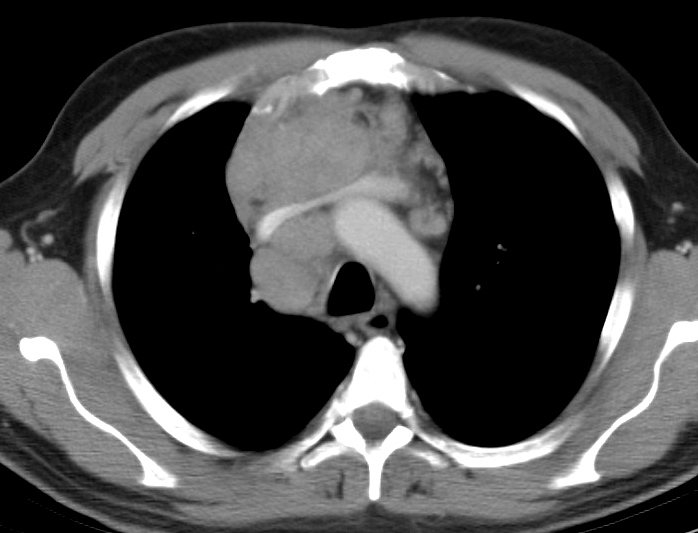

Gallery Mediastinum Lymphoma 10d

10d